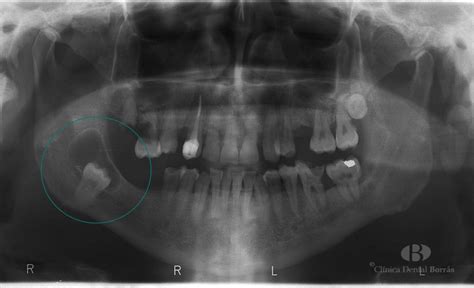

Un quiste dental es una pequeña bolsa llena de líquido, aire o células que se forma en relación con un diente. Este problema es más común de lo que imaginas. Por lo general, se detectan en radiografías de rutina y, aunque suelen ser benignos, es importante tratarlos para evitar complicaciones. Si tú o alguien que conoces tiene un quiste dental, no te alarmes, pero sí es fundamental que acudas a tu odontólogo lo antes posible.

- Quistes Dentígeros: Se forman alrededor de un diente que aún no ha erupcionado, debido a la acumulación de líquido entre la corona del diente y la capa externa del esmalte.

Aunque la mayoría de los quistes dentales son benignos, en raras ocasiones, pueden volverse malignos. Por eso, es vital realizar visitas regulares al dentista, incluso si no tienes síntomas, para detectar cualquier quiste mediante un estudio radiológico y determinar su naturaleza a través de una biopsia y estudio microscópico si es necesario.